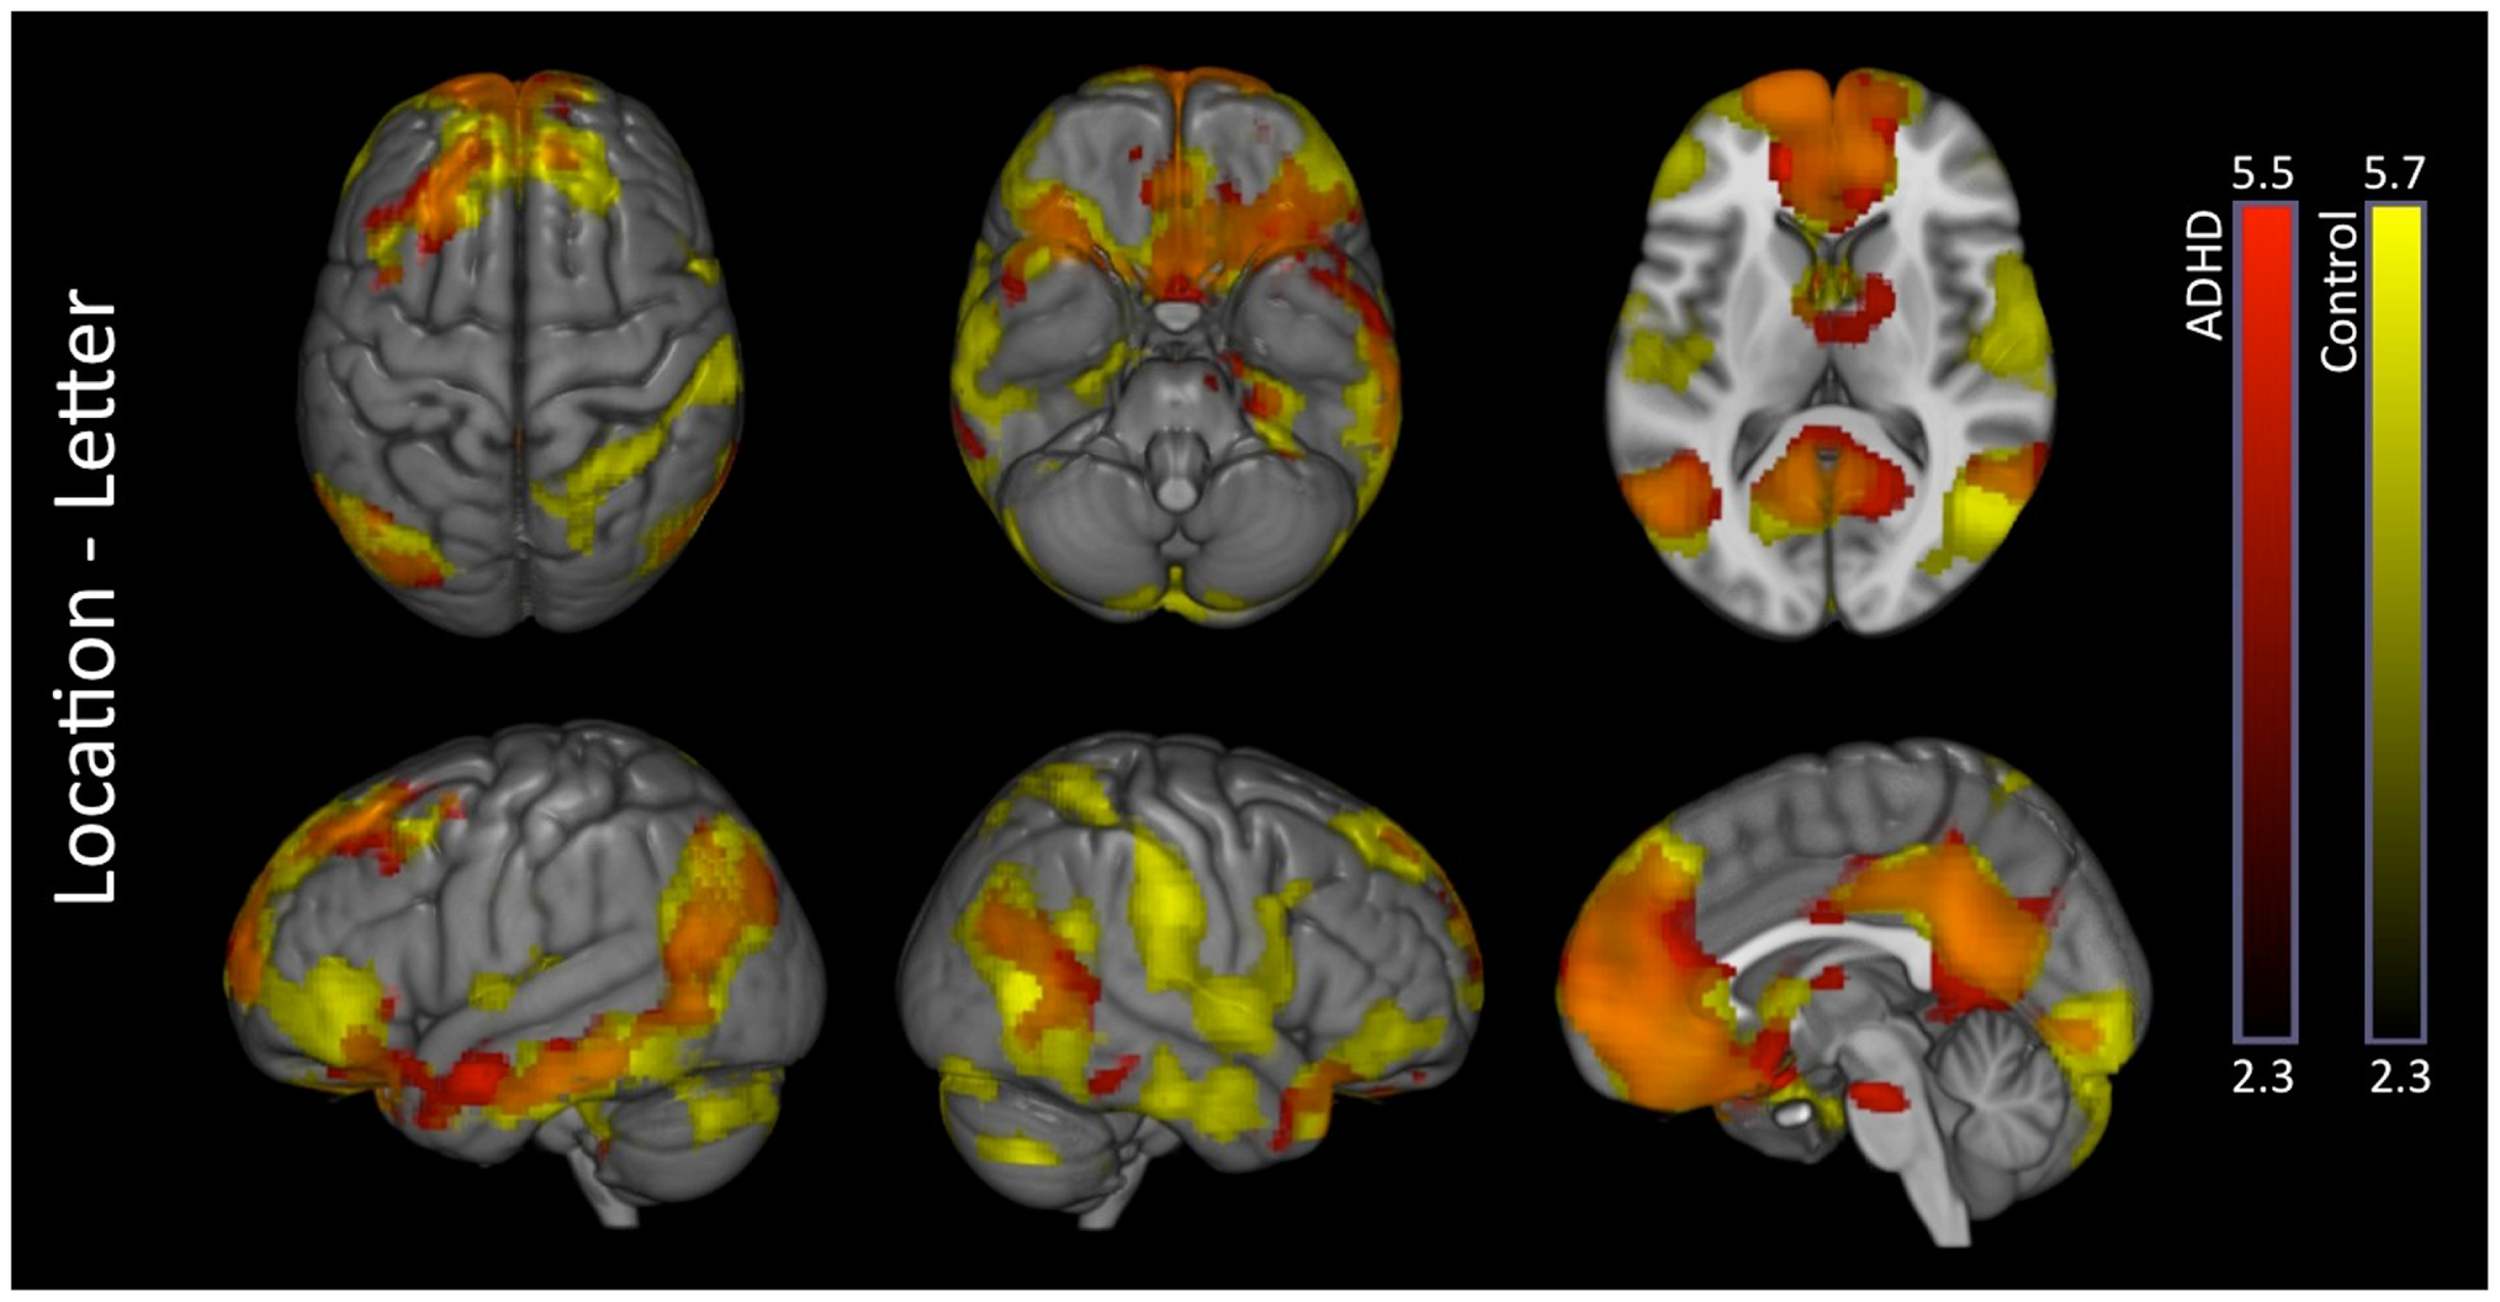

Location–letter

Attention-deficit hyperactivity disorder and control subjects exhibited several overlapping activations in brain regions associated with the DMN (medial prefrontal, medial parietal, and inferior parietal cortices). Additional unique activations were evident in subcortical regions among ADHD subjects, and within somatomotor regions among in controls (Figure 3 – see Part 2 in Supplementary Material for details). Direct comparison between the groups did not show significant differences.

Figure 3

Location–letter: within-group effects. Within-group analysis of location–letter contrast revealed several overlapping activations among ADHD (red) and control subjects (yellow) likely reflective of greater DMN activation during the location versus letter tasks. ADHD subjects showed additional unique activations in subcortical structures, while controls showed additional unique activations within somatomotor network regions. Overlap between the two groups is shown in orange. Images are thresholded using a voxelwise threshold of z = 2.3 and a cluster size probability of p < 0.05.